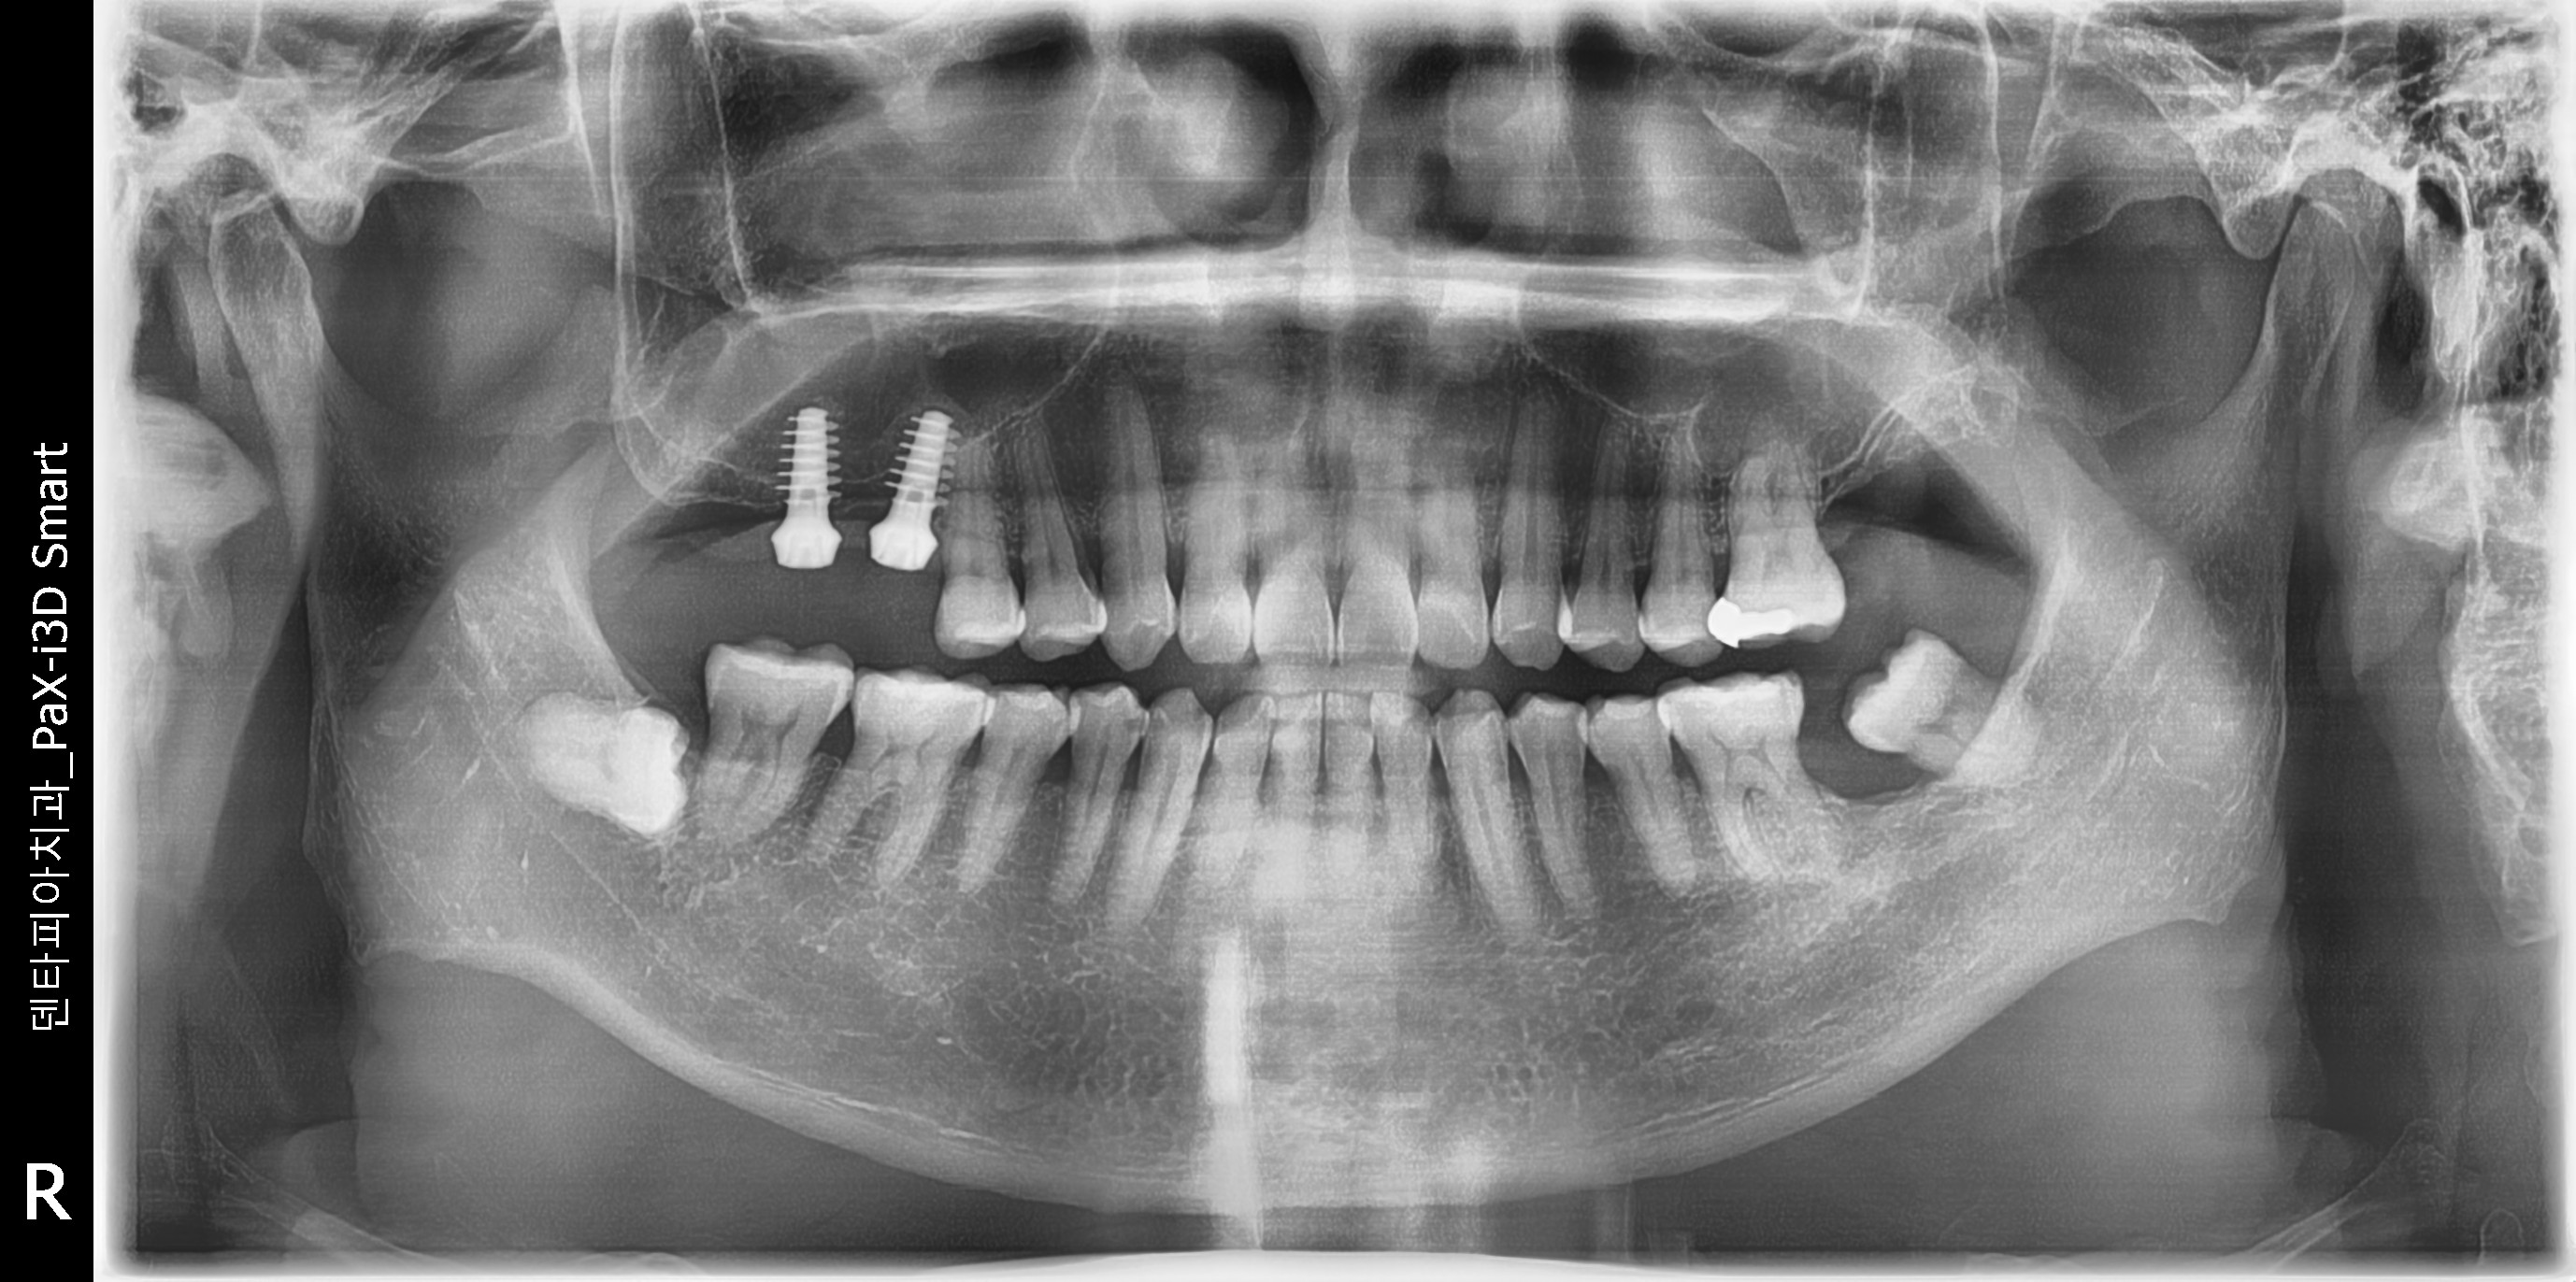

±è XX ´Ô 58¼¼

##16,17 Ä¡¾ÆÀÇ »ó½Ç

½Ä¸³ÈÄ ÆÄ³ë¶ó¸¶ »çÁøÀÔ´Ï´Ù.»ó¾Çµ¿ °Å»óÀ» ÁøÇà ÇßÀ¾´Ï´Ù.À̰͵µ ÀÕ¸ö Àý°³¸¦ ÇÏÁö ¾Ê°í »ó¾Çµ¿ ¸·À» °Å»óÇѰæ¿ìÀÔ´Ï´Ù.

¸·ÀÌ ¿Ã¶ó°£°Ô º¸À̽óª¿ä.